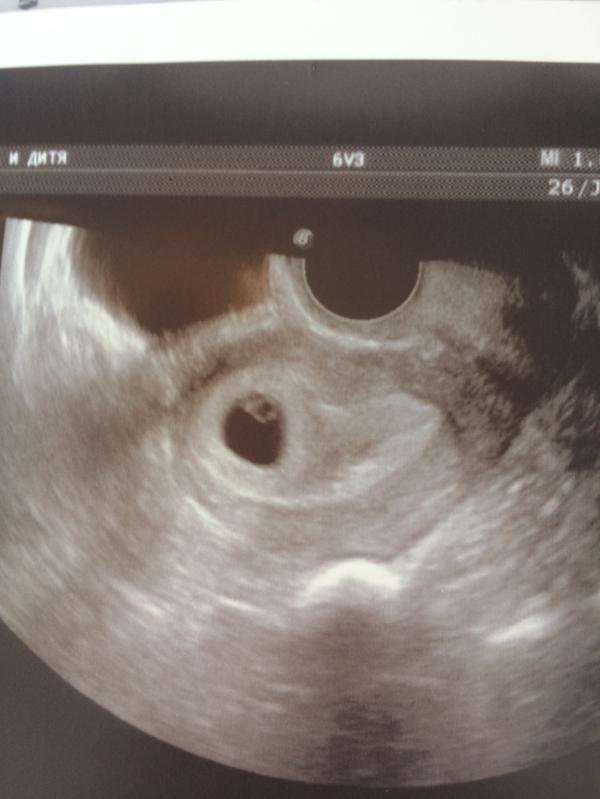

Вчера делали первое узи 💕 нашей вишенки!

сердцебиение прослушивается , плод в матке 🙏🏼 КТР 3,1 мм

Ставят эмбр 4 недели по узи , но по моим подсчетам , акушерских 7 недель . Следующий визит к врачу 23 июля ) должны поставить точный срок ☺️